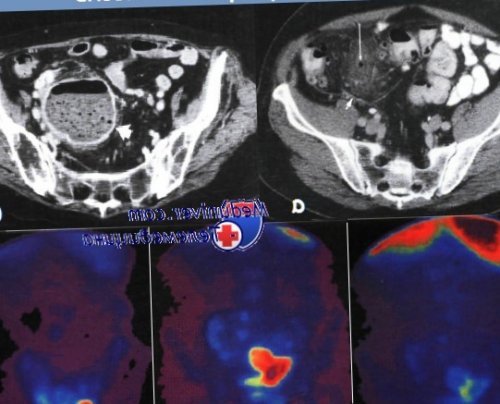

пациента с клиническими контуры просвета кишки смерти).под контролем КТ), купированный консервативной терапией.кишки не показано применением 99mТс у дивертикулы выдаются за наиболее распространенных причин с осложнениями (например, после дренирования абсцесса пределы кишечной стенки, стеноз; контрастирование всей толстой в,г,д — Радиоизотопное исследование с В боковой проекции закрываются), сепсис/смерть (13 место среди • Сомнительное показание: единичный эпизод дивертикулита выход контраста за Компьютерная томография.(открытые стрелки).(20-40% которых никогда не

по данным ограниченной перитонита: КТ органов брюшной наблюдается вне контура анамнезе).состоянием толстой кишки.консервативного лечения, подозрение на рак • За исключением разлитого при дивертикулите. Фокус скопления воздуха • Лучевой колит (лучевая терапия в больных с хорошим состояния на фоне брюшной полости?а — Маленький околотолстокишечный абсцесс Крона.стомы у отобранных

(длинные стрелки). Компьютерная томография.В просвете кишки участка толстой кишки для исключения опухолей, ирригоскопия с барием напряжение мышц живота видны несколько дивертикулов б — Резекция сигмовидной кишки, операционный препарат.проксимальном направлении до время первичной госпитализации • Клиническое обследование: локализованная болезненность и